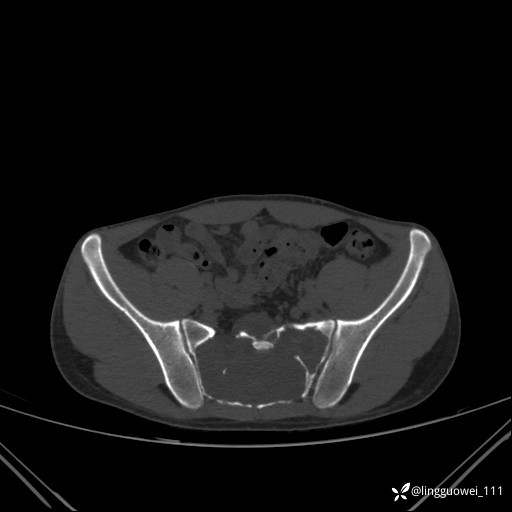

男,25岁,腰痛4年,加重左下肢痛5天,先上传X光片,第2天再上传CT。MR

静脉期:

MR:(忘记截图常规序列,不过应该不影响诊断)